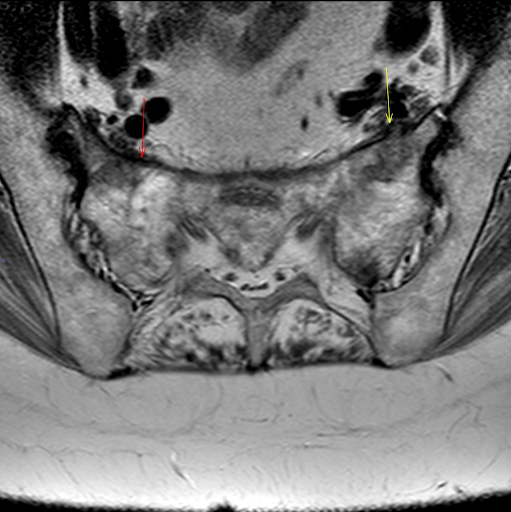

Figura 4: RMN arătând fractură de insuficiență sacrală pe fond de osteoporoză și paratiroidectomie

the msk playbook spinal insufficiency fractures

Figura 5: RMN arătând fractură de insuficiență sacrală pe fond de osteoporoză și paratiroidectomie

Figura 6: RMN arătând fractură de insuficiență sacrală pe fond de osteoporoză și paratiroidectomie